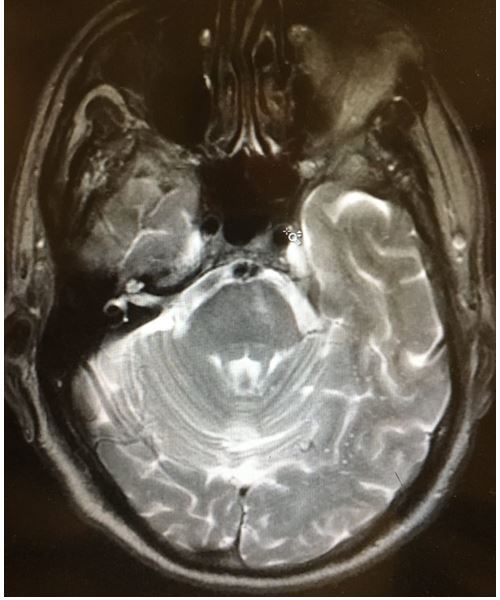

Initial diagnostic testing. CBC and BMP are normal, including potassium; MRI of the head is shown here.